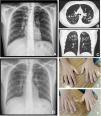

A twenty-two years old male, with a history of allergic asthma and rhinitis since childhood, with no current follow-up. No smoking or relevant family history. He presented with weakness of upper right limb, and muscle cramps, for four months. In association, he referred to worsening of cough and sputum. The neurologic examination revealed atrophy of the right forearm and arm, hyperreflexia and weakness of the upper limbs. Besides the presence of fever, the physical examination was normal. The patient was admitted to the Neurology department for clinical evaluation. Laboratory studies showed a slight elevation of infection markers. Arterial blood gases test were normal. Brain/vertebral magnetic resonance imaging and electromyography (EMG) were normal. Chest computed tomography scan showed cylindrical bronchiectasis with wall thickening, with a tree-in-bud micronodular pattern (Fig. 1, panel A–C). Due to recurrent respiratory infections since childhood, with cough and chronic bronchorrhea and, isolation of methicillin-susceptible Staphylococcus aureus in bronchial secretions, CF was suspected. The sweat test was 91mmol/L, and the genetic study identified p.Val232Asp and p.Phe508del mutations. Both neurological and respiratory symptoms improved with antibiotic therapy, so the patient was discharged. He began follow-up and treatment at the CF outpatient clinic, and radiological improvement was noticeable (Fig. 1 – panel D). No other organ involvement was observed. Spirometry revealed moderate obstructive ventilatory pattern (FVC: 2690mL/62.9%; FEV1: 2440mL/65.9%). For the following three months, he experienced worsening of the neurological deficits, with severe weakness of the four limbs (upper right limb with muscle atrophy, Fig. 1 – panel E–F), with an abnormal gait. Repetition of EMG showed neurogenic injury and active denervation, and with the clinical background were indicative of a definitive ALS diagnosis. At this point, he was experiencing a decline in respiratory muscle function, with a VC of 2100mL, decreasing 15% in the supine position, a peak cough flow of 270L/min and elevation of partial carbon dioxide pressure (47.8mmHg). Home mechanical ventilation was initiated with NVS (assisted/controlled mode, with oronasal mask) during sleep, and cough assistance techniques were optimized. Although he had not reported orthopnea or other sleep related symptoms, after beginning NVS he reported better sleep quality without orthopnea and a global improvement during the day; symptoms that he previously undervalued. Palliative care team was also involved.

Panel A, B and C: Chest x-ray and thoracic computed tomography showed cylindrical bronchiectasis with wall thickening associated with a tree-in-bud micronodular pattern; Panel D: Chest x-ray with radiological improvement, after CF therapy was initiated; Panel E-F: severe weakness of upper limbs (worse in the upper right limb with muscle atrophy).